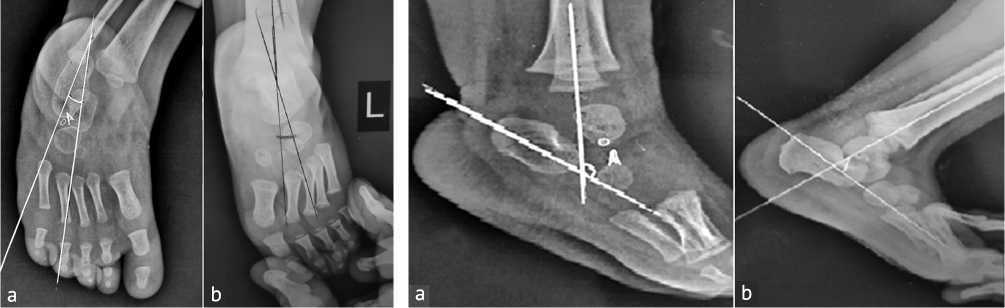

Talocalcaneal Angle measures hindfoot alignment since decreased angles indicate residual varus. This angle was measured by obtaining an anteroposterior (AP) radiograph of the foot. Identify the central axis of the talus (line drawn along the talar body and neck) and the central axis of the calcaneus. Measure the angle formed by the intersection of these two lines. The normal value range between 25º and 40º. Below this value indicates residual varus deformity (Fig. 1).

Tibiocalcaneal Angle evaluates ankle position and Achilles tendon flexibility. This angle is measured by obtaining a lateral radiograph of the ankle. Identify the longitudinal axis of the tibia and the axis of the calcaneus. Measure the angle formed at the intersection of these two lines. Between 60º to 90º is the normal value and any increase in this value is considered as equinus deformity (Fig. 2).

Fig. 1. Talo-calcaneal angle: (a) classic Fig. 2. Tibiocalcaneal angle: (a) classic view; (b) stress view view; (b) stress view